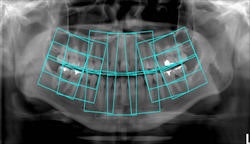

Top, standard panoramic image from a PC-1000 system using a CdTe sensor from Ajat and the PanoACT-1000 tomosynthesis software. Middle, although the anterior teeth are distorted, the posterior teeth no longer have overlapped interproximals. By manually positioning the patient in the system, the contacts are now open. Bottom, the tomosynthesis software then autocorrected the image to bring the front teeth into focus. All images courtesy of Dr. Robert Langlais. |